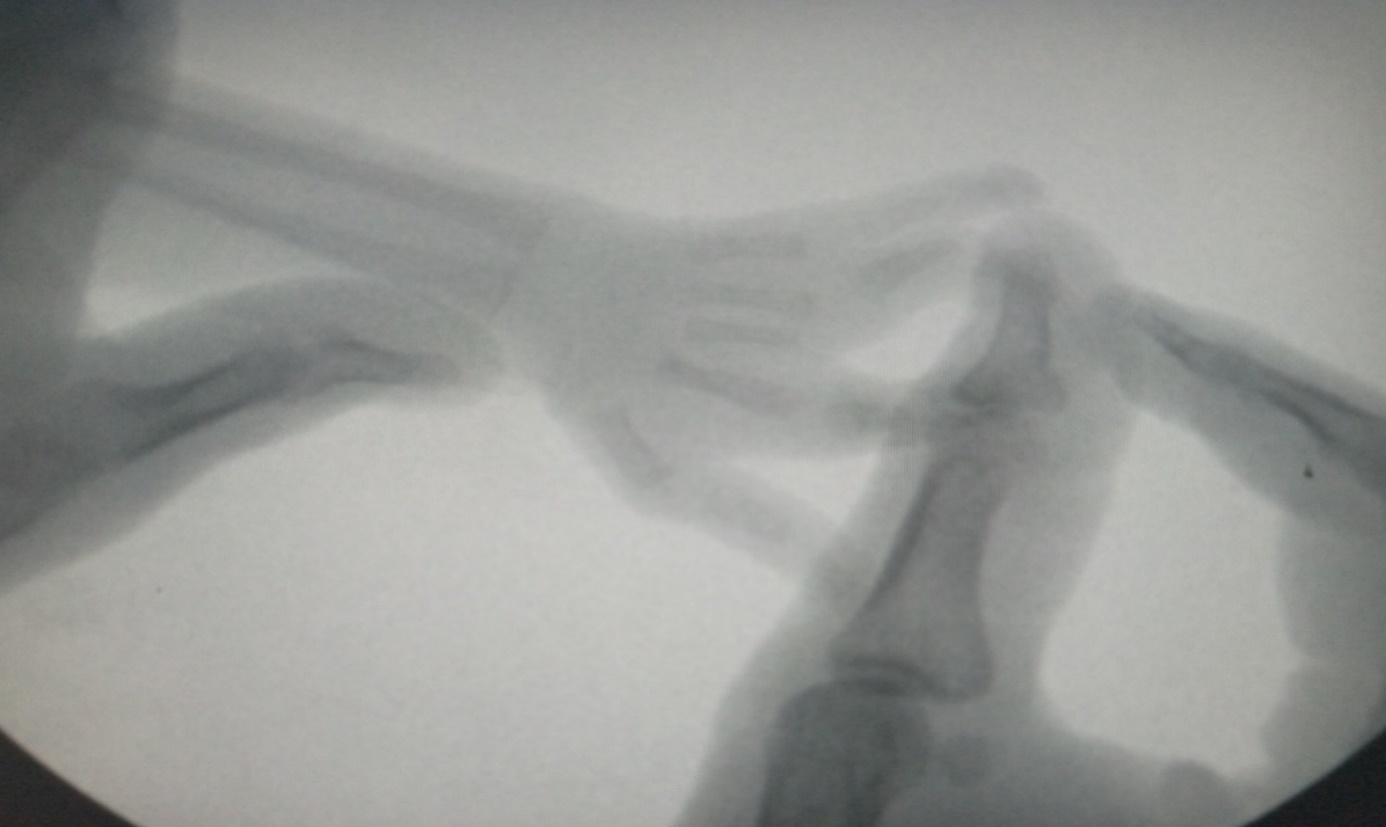

Plain radiograph of the right hand showed absence of the 3rd digit with partial fusion of the 4th web space proximally to the region of the distal ends of the proximal phalanges of the 4th and 5th digits. The remaining demonstrated digits and the metacarpals are within normal limit (figure 6).

Figure 6: Fluoroscopic and plain radiographic images of the right-hand demonstrating partial fusion of the soft tissues of the 4th web space proximally with associated absence of the 3rd digit. The remaining demonstrated bones appear within normal limit. Note however the digits of the care-giver to stabilize the patient’s hand for the imaging.